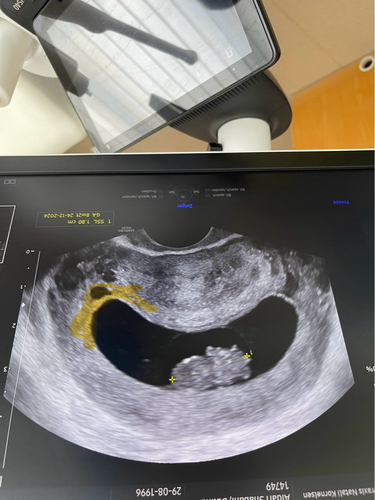

Kan iemand mij helpen met de placenta te herkennen? Ik las over de ramzi theorie? Zijn jullie hier ook bekend mee? Ik ben nu super benieuwd waar bij mij de placenta zit. Het is een inwendige echo Ik las dat de echo dan niet gespiegeld hoeft te worden?

Links boven placenta echo inwendig als ik het goed begrijp dan zou het een meisje moeten zijn volgens de ramzi theorie

Dat is juist geweest, heb toen een dochter gekregen 🤭

Kan iemand zien waar mijn placenta ligt ?